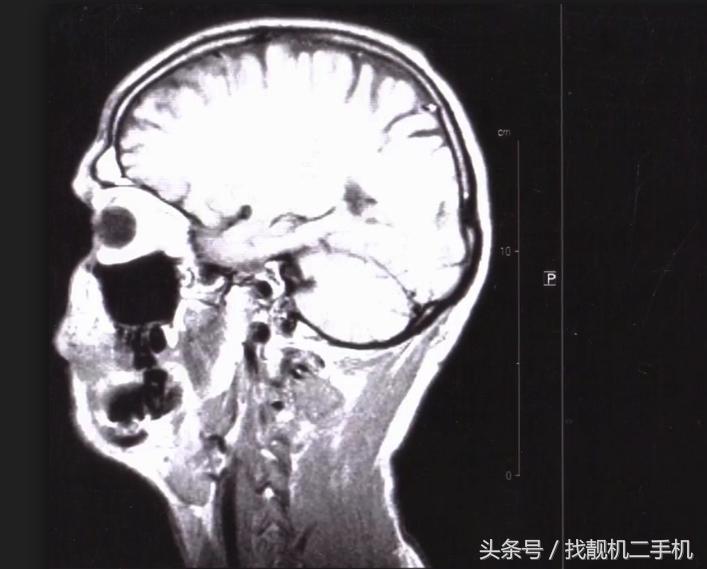

但卡伦教授已经很长时间没去实验室了,为什么还会有这种症状呢?这是因为有机汞的毒性是缓慢发作的,汞元素进入人体后,会大量聚集在大脑当中 破坏神经元,而且肝脏根本没办法应该对这种毒素。

医生也尝试着用了许多药物来清除她体内的有机汞,但还是束手无策,最后,卡伦教授大脑受到严重的损伤,在医院抢救无效去世。